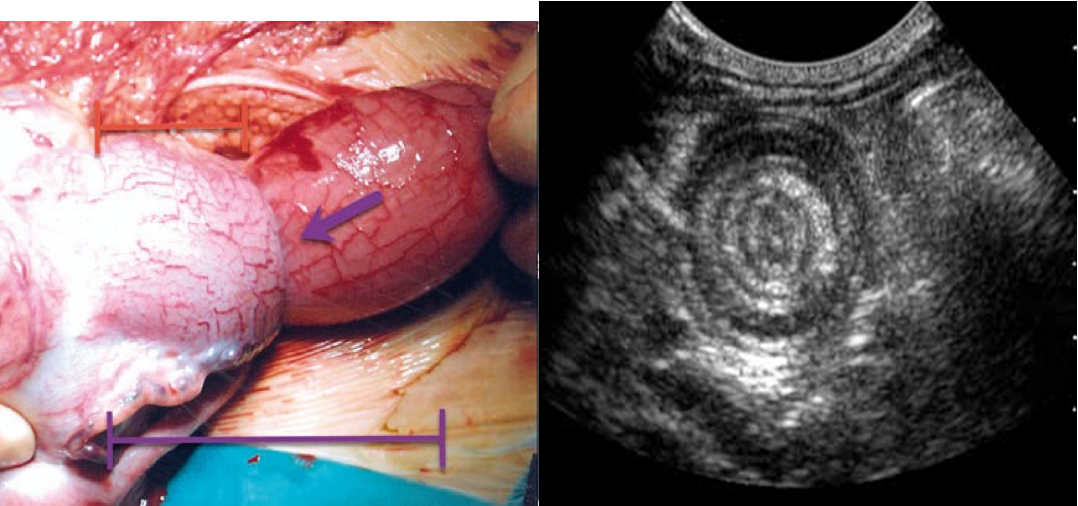

• Target sign : The invaginated portion of bowel appears as rings on a target on ultrasound.

• Pseudokidney sign: This “pseudokidney” is made up of longitudinal layers of bowel wall.

Target sign in intussusception Ultrasound abdomen (bowel; transverse plane) Concentric alternating hyperechoic and hypoechoic rings are visible. The hyperechoic rings (green overlay) are formed by mucosa and the hypoechoic rings (red overlay) by submucosa. Together the alternating layers produce a target-like appearance (target sign; bull’s eye sign).